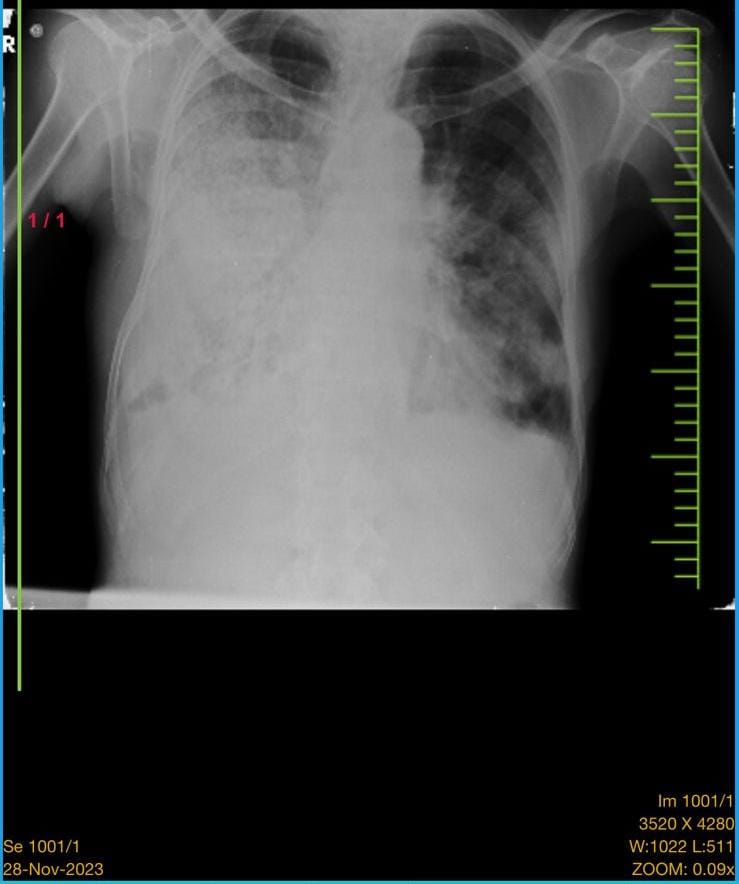

This is case of 83yr old male came with complaints of cough with sputum since 4 days,breathlessness since 4 days.

Provisional diagnosis: community acquired pneumonia.

After intubation et culture was done it shows klebsiella pneumoniaSerial chest x-ray before intubation (1-12-23)